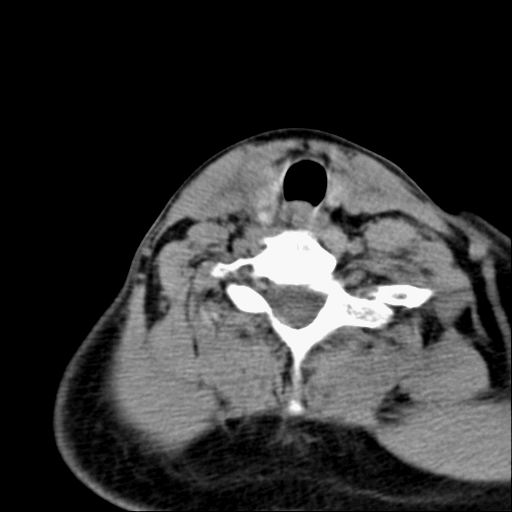

3.甲状腺肿:分结节性和弥漫性甲状腺肿。前者根据有无甲亢症状分为毒性和非毒性;后者包括桥本甲状腺炎和突眼性甲状腺肿,均属自身免疫性疾病。病理上桥本甲状腺炎可见甲状腺组织被大量淋巴细胞侵润,并形成淋巴滤泡,而突眼性甲状腺肿以滤泡增生为主要特征。

ct表现:甲状腺弥漫性增大,边缘清楚,密度均匀或不甚均匀,增强扫描有强化。结节状甲状腺肿尚可见在增大的甲状腺组织内有多发结节状低密度或高密度区,并常多发性钙化。

甲状腺腺瘤或癌,结合增强或彩超

右甲状腺占位,建议增强。

甲状腺右侧叶占位,定性困难,建议增强。

右侧甲状腺低密度病灶,性质待定;建议行进一步检查。